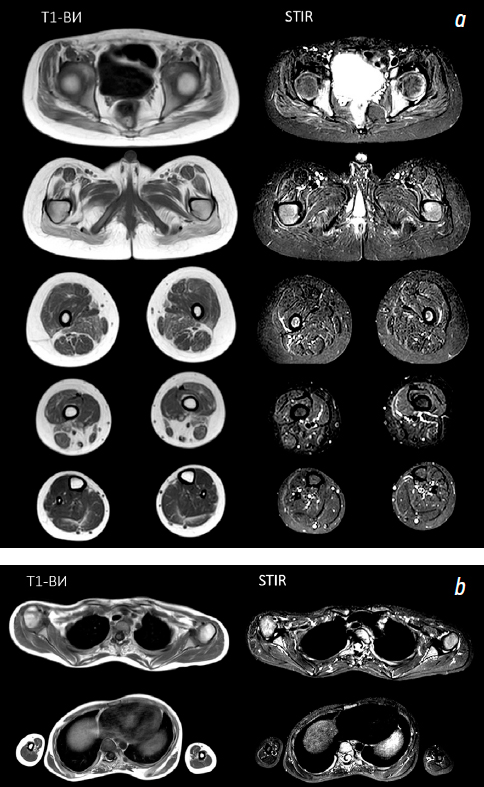

Магнитно-резонансная томография скелетных мышц

Пациенту выполнена магнитно-резонансная томография скелетных мышц плечевого, тазового пояса, бедер и голеней в аксиальных проекциях с применением протоколов Т1-взвешенных изображений и Short Tau Inversion Recovery (STIR). Оценена выраженность фиброзно-жировой дегенерации по шкале Mercuri [17] (табл. 2).

В тазовом поясе на Т1-взвешенные изображениях отмечены симметричная атрофия и фиброзно-жировая дегенерация скелетных мышц: в m. gluteus max. стадия IIb в проксимальных отделах и стадия III в дистальных отделах), m. gluteus medius и minumus стадия IIb, в m. tensor fasciae latae стадия IIа. Отмечены начальные изменения в m. adductor longus и brevis (стадия I). При оценке изображений в режиме STIR патологически измененного сигнала не выявлено. В области бедер на Т1-взвешенных изображениях отмечены симметричная фиброзно-жировая дегенерация и атрофия мышц. Обнаружена полная фиброзно-жировая дегенерация m. semimembranosus с двух сторон (стадия IV). Наибольшее поражение можно наблюдать в m. sartorius (стадия III), m. adductor magnus и m. biceps femoris (стадии IIb–III). Отмечена умеренная жировая дегенерация в m. semitendinosis, m. rectus femoris, m. vastis lateralis, m. vastis medialis и m. intermedius (стадия IIа). Начальные изменения в m. gracilis (стадия I). В режиме STIR данных о патологическом измененном сигнале не выявлено. В области голеней отмечена фиброзно-жировая дегенерация с двух сторон m. soleus и m. gastrocnemius (стадия IIа), начальные изменения в m. tibialis anterior, m. peroneus (стадия I). При оценке изображений в режиме SITR гиперинтенсивный сигнал не обнаружен (рис. 4, a).

Рис. 4. Магнитно-резонансная томография скелетных мышц: a — тазового пояса, бедер и голеней пациента; b — плечевого пояса пациента. Т1-ВИ — Т1-взвешенные изображения; STIR — восстановление короткой тау-инверсии

Fig. 4. Magnetic resonance imaging of the skeletal muscles: а, of the pelvic girdle, thighs and legs of the patient; b, of the shoulder girdleof the patient. Т1-ВИ, T1-weighted images; STIR, Short Tau Inversion Recovery

В области плечевого пояса отмечены симметричная атрофия и фиброзно-жировая дегенерация скелетных мышц: выраженные изменения паравертебральных мышц (стадии III–IV), умеренные изменения в m. biceps brachii, m. deltoideus, m. pectoralis major и minor (стадия I). В режиме STIR данных о патологическом измененном сигнале не выявлено (рис. 4, b).